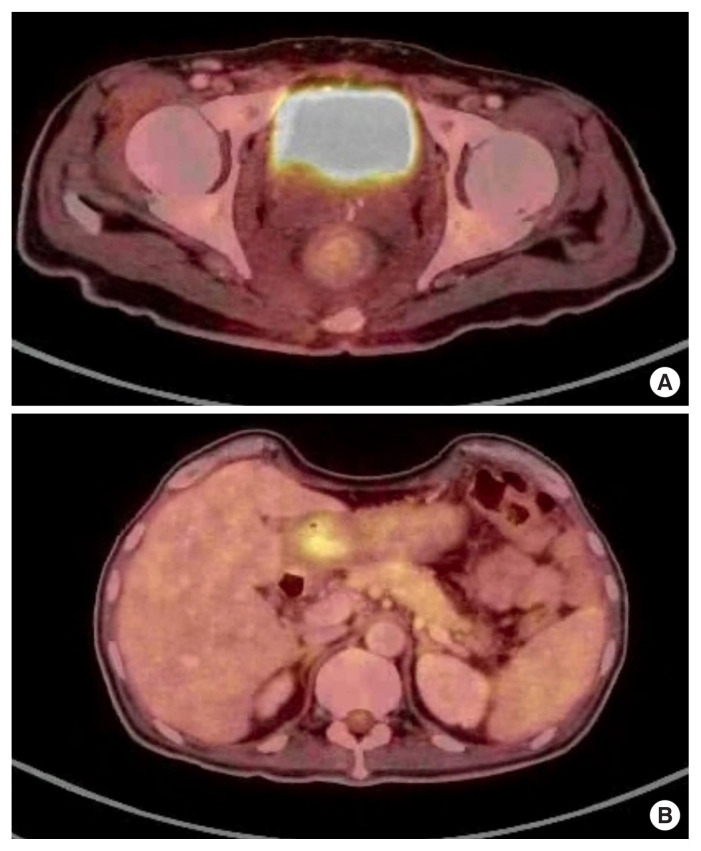

转移到直肠是非常罕见的,通常是由乳房,胃肠道和泌尿生殖系统的原发引起的。我们在这里报告一个病例急性肠梗阻引起一个不寻常的直肠狭窄,他接受了转移口。在对直肠狭窄的病因进行广泛评估后,他被诊断为弥漫性胃癌并伴有Schnitzler转移到直肠粘膜下层。这是一种不寻常的转移类型,非常罕见。文献中仅报道了11例此类病例。

Metastasis to the rectum is very rare and is usually caused by primaries from the breast, gastrointestinal tract, and genitourinary system. We report here a case of acute intestinal obstruction caused by an unusual rectal stenosis, for which he underwent a diversion stoma. On extensive evaluation for the etiology of the rectal stenosis, he was diagnosed with diffuse gastric cancer with Schnitzler's metastasis to the rectal submucosa. This is an unusual type of metastasis, very rarely seen. Only 11 such cases have been reported in the literature.